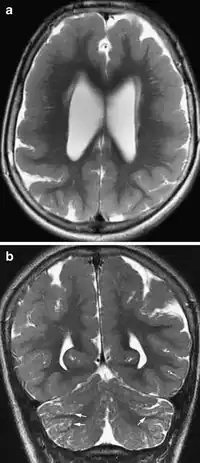

- Radiological findings (MRI) demonstrated symmetric generalized polymicrogyria with decreasing anterior-posterior gradient, most prominent in frontoparietal cortex.[5]

- Numerous gyrus on the cortex

- Small gyri and sulci

- Thin cortex

There are different tests or methods used to determine GPR56 expression or visuals of the brain to analyze the specific sections that are affected. These tests for example, using animals such as mice, RNAi, Behavioral assay, Electron microscopy, CT scan, or MRI demonstrate different results that concludes an affected BFPP patient.[16] MRI's reveal either irregularity to the cortical surface suggestive of multiple small folds or an irregular, scalloped appearance of the gray matter-white matter junction.

Neuroimaging The diagnosis of polymicrogyria is typically made by magnetic resonance imaging (MRI) since computed tomography (CT) and other imaging methods generally do not have high enough resolution or adequate contrast to identify the small folds that define the condition. The cerebral cortex often appears abnormally thick as well because the multiple small gyri are fused, infolded, and superimposed in appearance.[5]